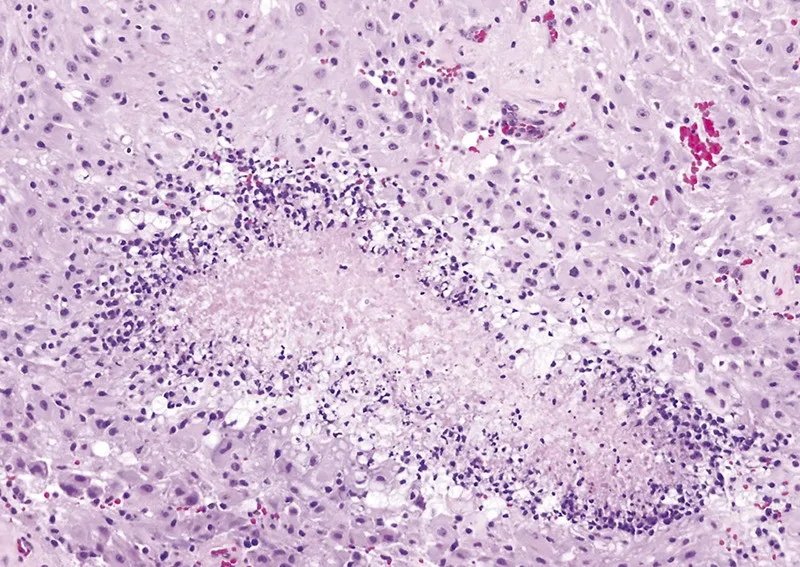

室管膜下巨细胞星形细胞瘤属于边界清楚的星形细胞瘤,属WHO 1级。室管膜下巨细胞星形细胞瘤常为伴发于结节性硬化的少见良性星形细胞肿瘤.占结节性硬化患者的10%~15%,病理学特征为由巨噬细胞样星形细胞构成的室管膜下巨细胞星形细胞瘤与结节性硬化和错构瘤共存。肉眼所见肿瘤为边界清楚的分叶状肿块,常见钙化、囊变和丰富的血管。镜下典型者呈双核或多核星形细胞瘤,常见囊变,分化良好,可见两核或多核形成,有丝分裂少见。

CNS WHO 1级命名不因有丝分裂活性(A)、少见的微血管增生(B)或坏死(即使栅栏状)(C)而改变。

CNS WHO 1级命名不因有丝分裂活性(A)而改变。

CNS WHO 1级命名不因少见的微血管增生(B)而改变。

CNS WHO 1级命名不因坏死(即使栅栏状)(C)而改变。